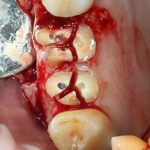

Простой синуслифтинг. Часть I.